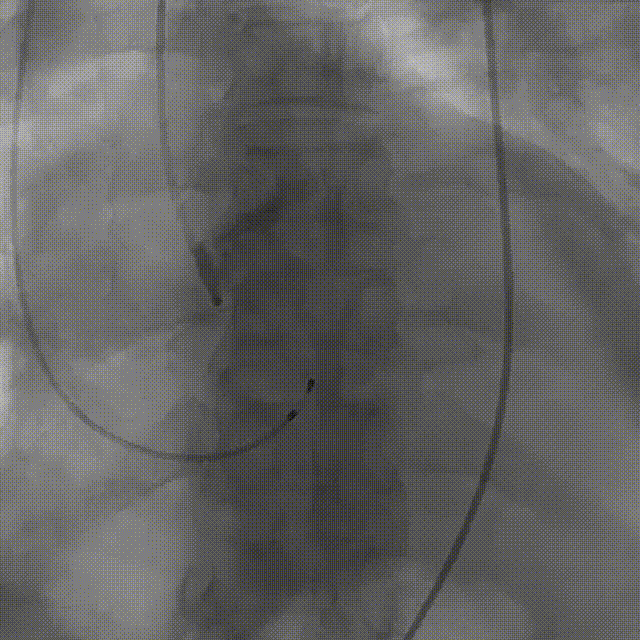

手术影像:

左冠造影灌注良好

右冠造影灌注良好

主动脉根部造影,狭窄伴反流

导丝顺利跨瓣

23mm球囊预扩无腰征,微量漏

输送器柔顺过弓、跨瓣

瓣膜开始零位定位

瓣膜逐步释放到工作位

工作位造影位置良好

瓣膜逐个脱钩

完全释放后造影,膨胀不良,有漏

25mm球囊后扩

后扩后瓣膜形态良好,造影基本无漏

外周血管造影检查良好